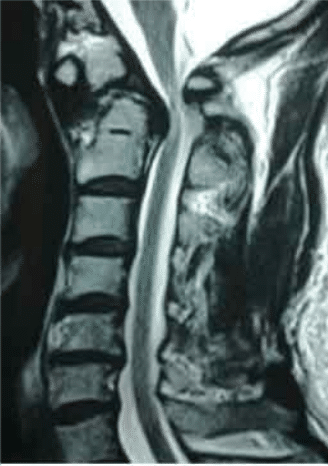

Anterior arch of C1 subluxes anteriorly narrowing the space available for cord. This is seen on MRI scan. The space available for cord widens on neck extension.Investigations

Investigations showed C1-C2 subluxation from Os Odontoid Eum. This was reducible on neck extensions.